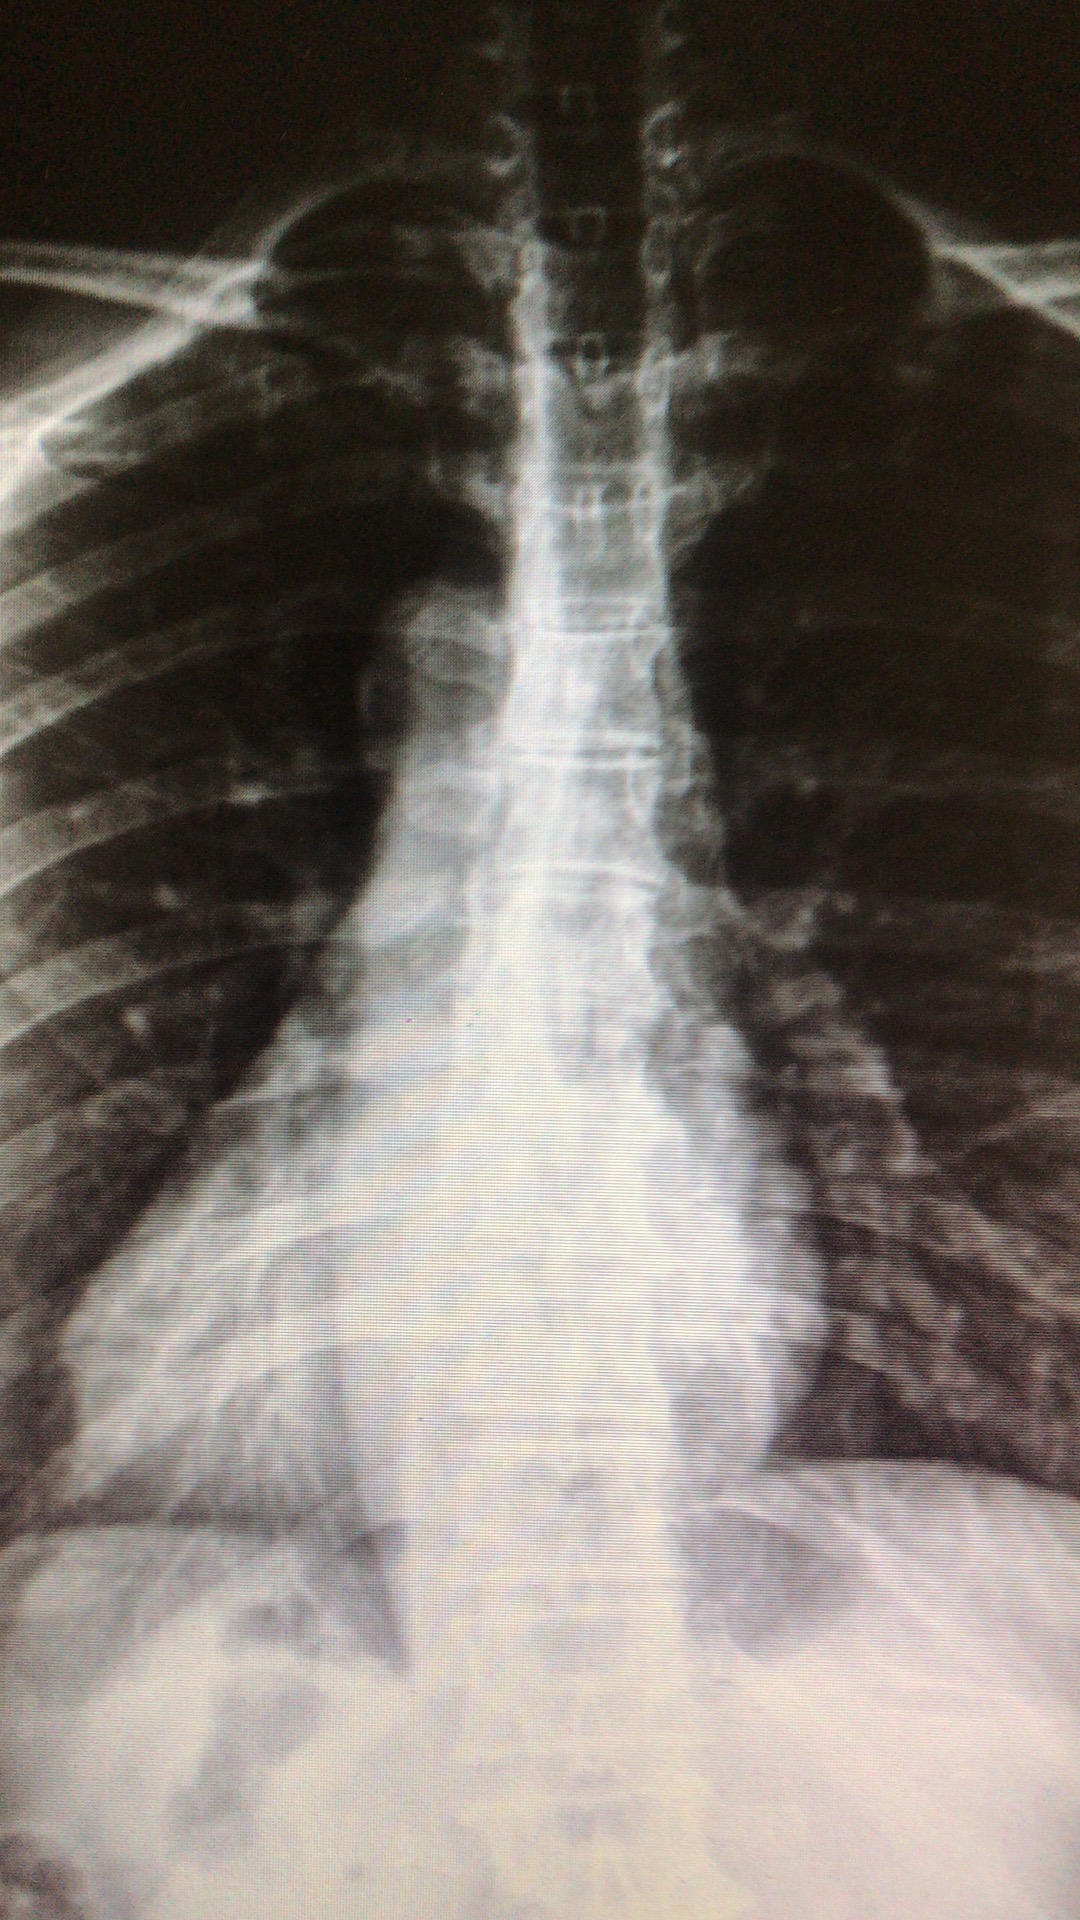

在门诊,接诊的康复医学科游菲主任让张平做一个动作:站在平地上,双手掌合十放在双膝之间,逐渐弯腰。在张平弯腰后,游主任发现,他左侧背部明显高出左边一截,随后的X片里,脊柱呈现一个S型。由于脊柱侧弯严重,压迫了内脏,张品刚才会有不舒服和内脏长反了的感觉,且对他的精神功能也造成了影响。

针对病情,康复系学科医生通过对张平姿势评估及精准的影像X光专科画片,测量他每个椎体间的距离和位置改变,获得精确的数据后,制定了针对性手法矫正治疗方案将错位的椎体复位。在接受了三次治疗后,张平的恢复情况良好。